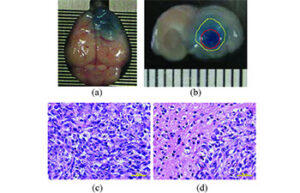

- Mice and rat brain edema test

- Mice and rat brain TTC test

- Evaluation of brain Evans blue staining test in rats and mice